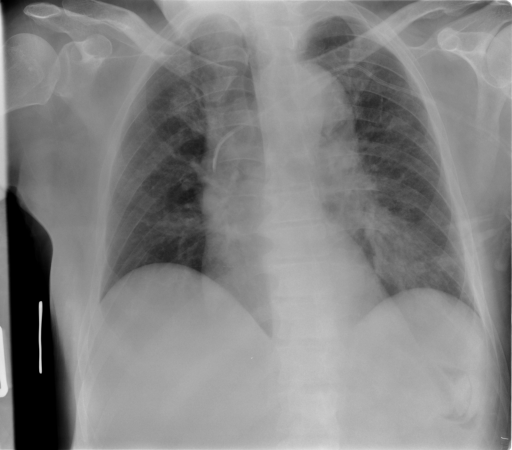

Image Dataset – The Image Retrieval in Medical Applications (IRMA) 2009 database is a collection of 14,410 x-ray images that have been randomly collected from daily routine work at the Department of Diagnostic Radiology of the RWTH Aachen University (Fig. 2). The downscaled images were collected from different ages, genders, view positions, and pathologies [33]. Each image in the dataset has an IRMA code. According to these codes, 193 classes are defined according to 2008 IRMA codes. The IRMA code comprises four axes with three to four positions each: 1) the technical code (T) (modality), 2) the directional code (D) (body orientations), 3) the anatomical code (A) (body region), and 4) the biological code (B) (the biological system examined). The complete IRMA code consists of 13 characters TTTT-DDD-AAA-BBB, with each character in . As many as 12,677 images are separated for training. The remaining 1,733 images are used as test data. In this project, the IRMA 2009 dataset has been used with specified 2008 IRMA labels (consisting of 193 classes) for retrieval purposes. Otherwise, same dataset is utilized with general 2005 IRMA labels (consisting of 57 classes) for classification purpose. 2005 IRMA labels are more general than 2008 IRMA labels because it has been made of 6 characters from top of hierarchical classes, TT-D-AA-B. In 2009 dataset, each image can not have been coded according to 2005 IRMA coding regularity. A total number of 12,631 images from training set and 1,639 images from testing set have 2005 IRMA codes. For this reason, SVM classification is implemented on corresponding images.